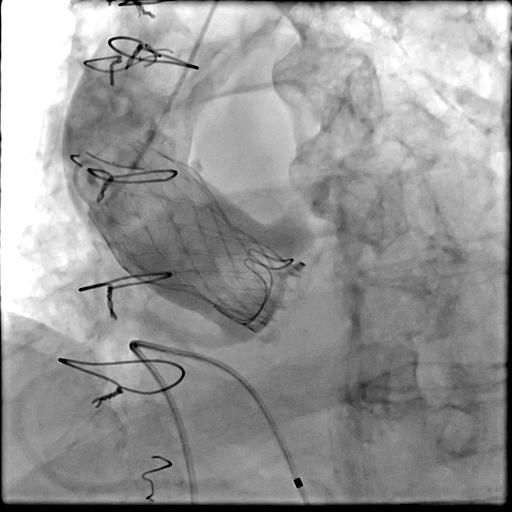

提供:メドトロニック(株)・エドワーズライフサイエンス(株)・アボットメディカルジャパン(同)

開胸術・大動脈弁置換術で手術された生体弁(人工弁の一つ)が10〜15年前後で劣化し(傷んで)、再手術が必要となることがあります。再手術では再開胸術(2回目の開胸術)が行われることもありますが、再手術としてカテーテル治療(TAVI)も可能となっています。(専門用語ではTAV in SAVやvalve in valveと呼ばれます。)

通常のTAVI同様に、患者さんの体への負担が非常に少ない治療となっています。